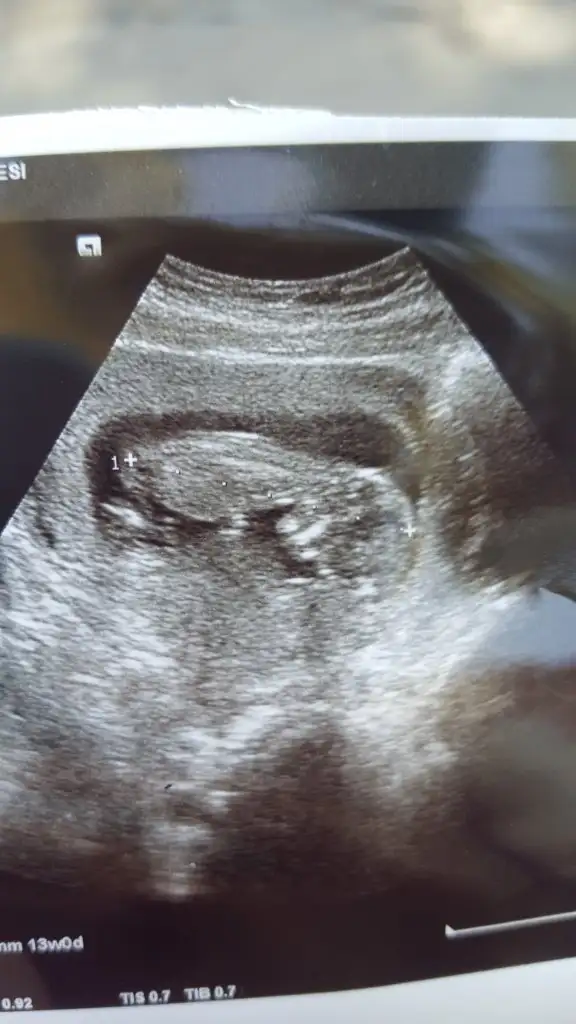

Emin değilim sanki kız ama emin değilim varsa başka USG paylaşın 11 12 13 haftalar olmalıİkra Meyra tahminin var mı.doktor göremedi.ters durmuş hareket etmedi hiçEki Görüntüle 2678263

Emin değilim sanki kız ama emin değilim varsa başka USG paylaşın 11 12 13 haftalar olmalı